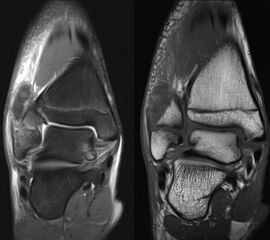

MRT

Die Kernspintomographie hat ihre Stärke in der Darstellung von Weichteilverletzungen. Insbesondere Verletzungen der Wachstumsfuge, des Periosts und der Bänder lassen sich gut visualisieren. Nachteilig ist die Untersuchungsdauer von 20-30 Minuten. Bleibt das Kind während dieser Zeit nicht ruhig liegen, kommt es zu Bewegungsartefakten, welche die Beurteilbarkeit der Bilder beeinträchtigen.

Os subfibulare

Multiple laminäre Ausrisse des fibularen Bandapparats aus der Fibulaspitze können zur Entwicklung eines Os subfibulare führen. Das Os subfibulare findet sich unterhalb der Fibulaspitze ventral der Peronealsehnen. Ohne Schmerzsymptomatik bzw. Aktivierung im MRT hat Das Os subfibulare keinen Krankheitswert. Ein mobiles Os subfibulare führt zu einer lokalen mechanischen Reizung teilweise in Verbindung mit einer Instabilität des Sprunggelenks. Im MRT zeigt sich eine Aktivierung des instabilen Areals. Bei anhaltenden Schmerzen besteht die Behandlung in einer operativen Entfernung des Knochens mit Refixation des Kapselbandapparats.

Os trigonum

Das Os trigonum lässt sich als isolierter Knochen dorsal des Talus seitlichen Röntgenbild darstellen. Normalerweise hat das Os trigonum keine klinische Relevanz. Bei entsprechenden Beschwerden und einer Aktivierung im MRT kann der Knochen arthroskopisch entfernt werden. Gehäuft beobachten wir eine mechanische Problematik durch das Os trigonum bei jugendlichen Fußballspielern und Tänzerinnen.

Ossifikationsstörung des Talus

Manchmal findet sich an der talaren Gelenksfläche eine lokale Störung der Ossifikationen. Wichtigste Differenzialdiagnose ist die osteochondrale Läsion. Die Ossifikationsstörung ist ein Zufallsbefund ohne klinische Relevanz. Kennzeichnend sind das fehlende Ödem und die intakte Knorpeloberfläche.

Osteochondrale Verletzungen

Osteochondrale Verletzungen können infolge eines Distorsionstraumas beobachtet werden (Taluskantenfraktur), teilweise lässt sich auch kein Trauma eruieren. Der es sich bei osteochondralen Verletzungen um keine Arthrose handelt, ist gerade bei Schmerzfreiheit ein defensives Vorgehen angezeigt. Bei offenen Wachstumsfugen kann eine osteochondrale Verletzung unter konservativer Therapie ausheilen.

Eine retrograde Anbohrung ist indiziert, wenn sich im MRT Verlauf eine zunehmende Sklerosierung im Randbereich der Läsion zeigt bei intakter Knorpeloberfläche.

Instabile Knorpelareale werden arthroskopisch entfernt in Verbindung mit einer Mikrofrakturierung der subchondralen Knochenlamelle.